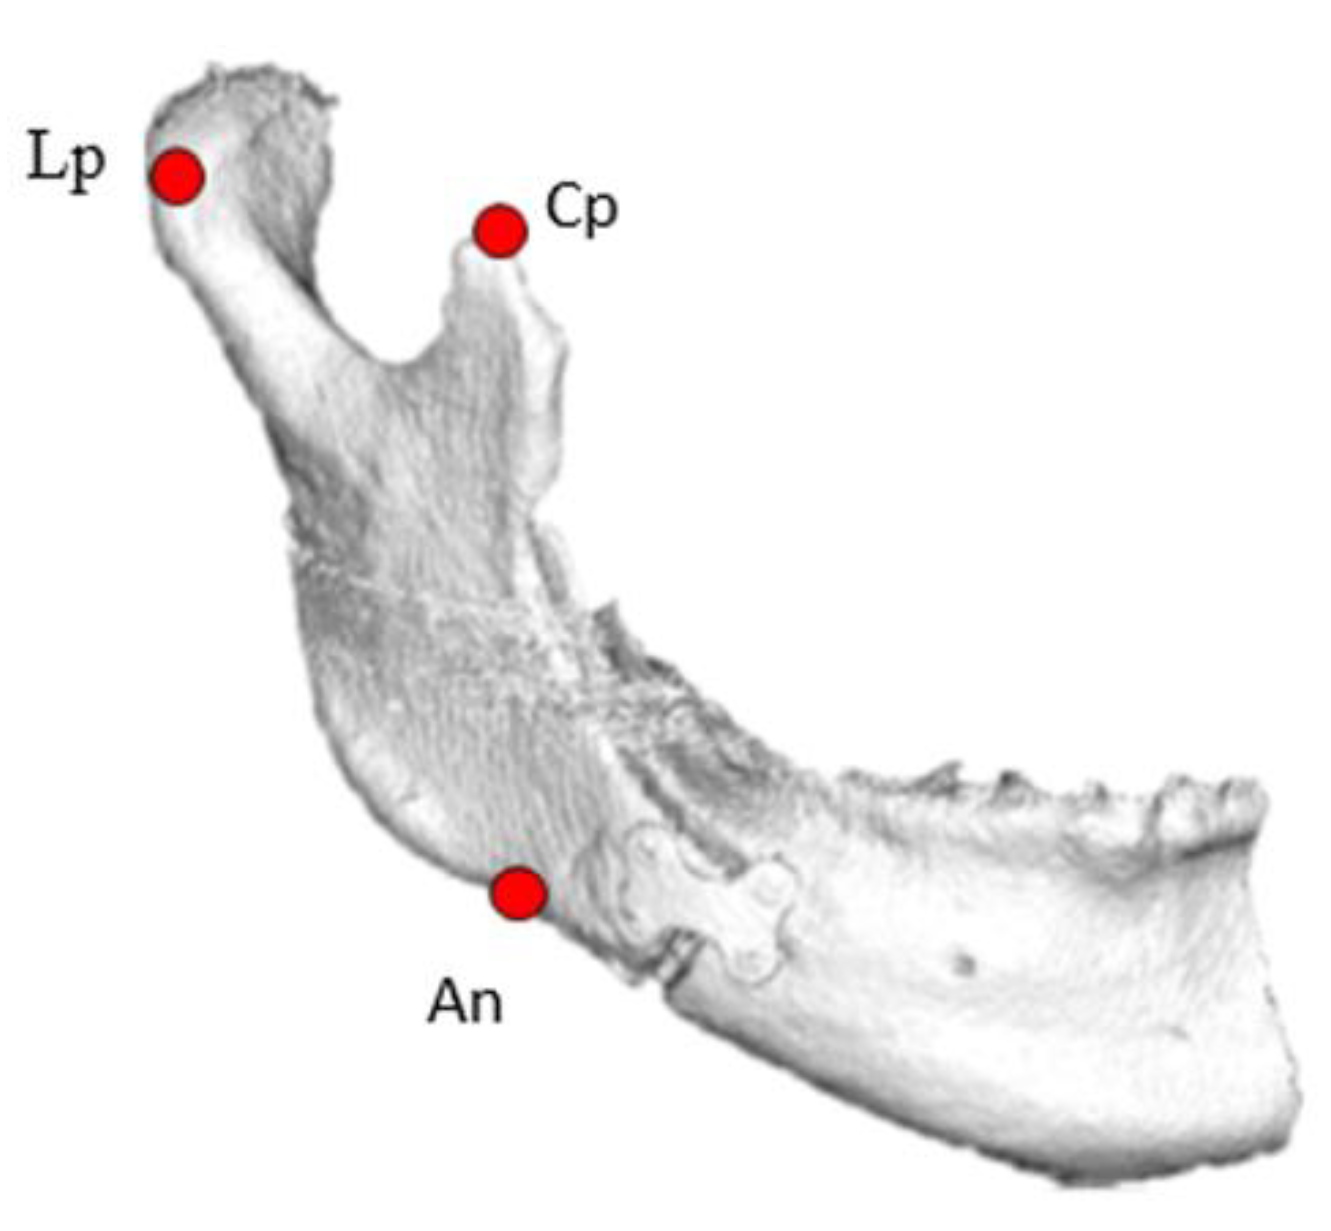

2.2.2. Three-Dimensional Computed Tomography (3D CT) Analysis

| X | Y | Z | θ | X | Y | Z | θ | |||||||||

| Mean | SD | Mean | SD | Mean | SD | Mean | SD | Mean | SD | Mean | SD | Mean | SD | Mean | SD | |

| Lp (mm) | −0.1 | 0.4 | 0.1 | 0.1 | 0.1 | 0.5 | −0.2 | 1.3 | 0.2 | 1.0 | 0.4 | 0.7 | ||||

| Cp (mm) | −0.1 | 0.4 | 0.1 | 0.5 | 0.2 | 0.6 | −0.7 | 2.3 | 0.1 | 2.5 | −0.2 | 0.9 | ||||

| An (mm) | 0.1 | 0.8 | −0.6 | 3.4 | −0.5 | 2.3 | −0.9 | 2.8 | 2.4 | 2.2 | −1.9 | 4.0 | ||||

| Condylar angle (°) | 3.0 | 1.1 | 3.0 | 3.9 | ||||||||||||